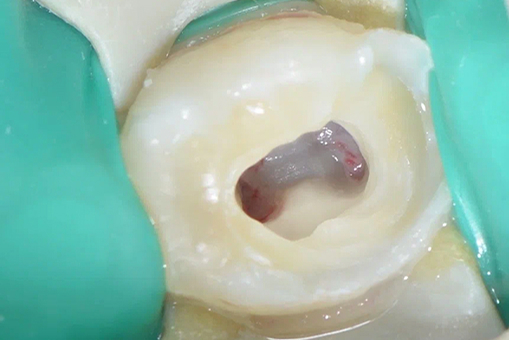

Сначала на десну наносится обезболивающий гель с минимальным риском аллергической реакции после которого проводится дальнейшая анестезия. Благодаря этому процедура проходит максимально безболезненно. Аккуратное удаление воспаленной пульпы в стерильных условиях с использованием латексного платка «Коффердама». Дезинфекция каналов. Специалисты "Руссдент" используют Био совместимые материалы для получения наилучшего результата.

До/после лечения